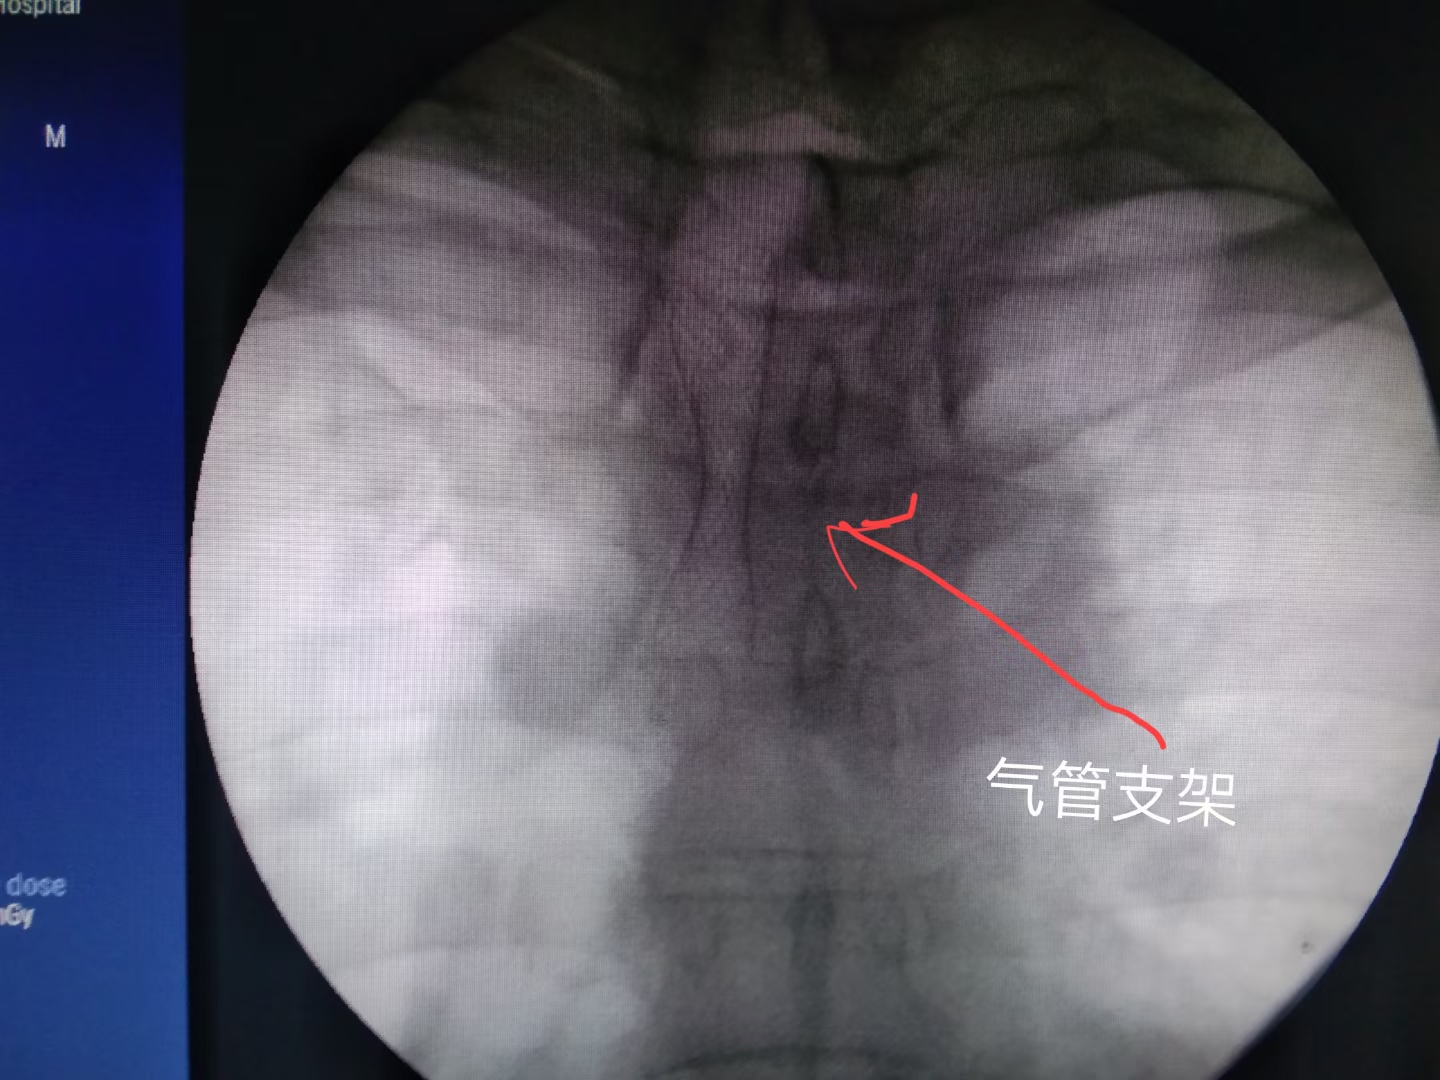

病例2

病例2图示为:肿瘤压迫气管狭窄患者,奔着放气管支架从外院转院而来。为其放气管支架一枚,手术关键步骤只需几分钟时间,解决重症呼吸困难立竿见影。